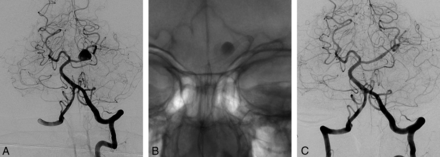

3D image (A) and lateral angiography (B) show a left paraophthalmic bleb aneurysm in a patient who had a subarachnoid hemorrhage 3 months earlier. Lateral angiogram 6 months after placement of a single PED of 3.75 × 12 mm (C) demonstrates complete occlusion of the aneurysm.

Right carotid angiogram (A) demonstrates a small carotid cave aneurysm in a patient who had an anterior communicating artery aneurysm previously treated with coiling following SAH. Six-month control angiography (B) shows occlusion of the aneurysm.